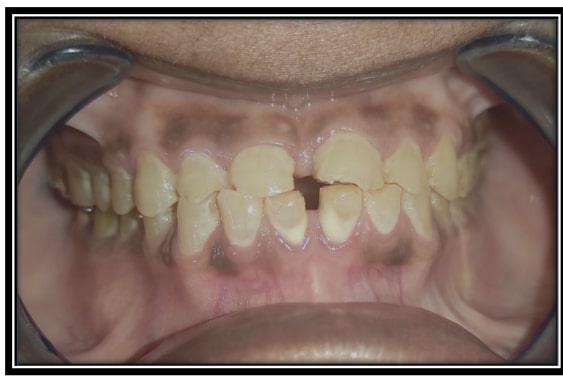

Some of Our sucessfull Smile FMR cases